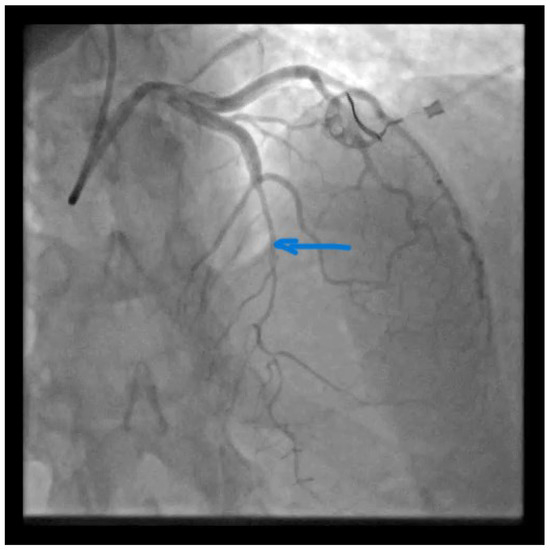

Figure 1.

Catheterization of the coronary artery showed spontaneous type 2B coronary artery dissection (SCAD) with thrombolysis in myocardial infarction (TIMI) with flow grade 2 of the left anterior descendent (LAD) coronary artery located in the medial distal segments (blue arrow) where stenosis extends to the end of the vessel (Video S1). SCAD is defined as a nonatherosclerotic or iatrogenic separation of the coronary arterial tunics with a non-traumatic cause, secondary to vasa vasorum hemorrhage or intimal tear, which creates a false lumen, coronary compression, and downstream myocardial ischemia [1]. The primarily affected demographic groups are young-to-middle-aged women [1]. This can sometimes be an unrecognized condition. SCAD can cause acute myocardial infarction (AMI) and sudden cardiac death [2,3]. A previously healthy 42-year-old woman presented to the emergency department with a complaint of gradually squeezing chest pain in rest which lasted for 2.5 h. She had also noticed vomitus and an increased blood pressure value of of 170/120 mmHg. She was admitted to the Cardiology Department at the University Clinical Center of Serbia. No previous diseases were found in her medical history. She underwent five normal deliveries and one spontaneous abortion. The last delivery was eight years ago. She did not use any hormonal therapy. No special family history was reported. In admission to the Coronary Care Unit, she was hemodynamically stable and without signs of heart failure. Her blood pressure was 120/80 mmHg and her heart rate was 98 bpm.